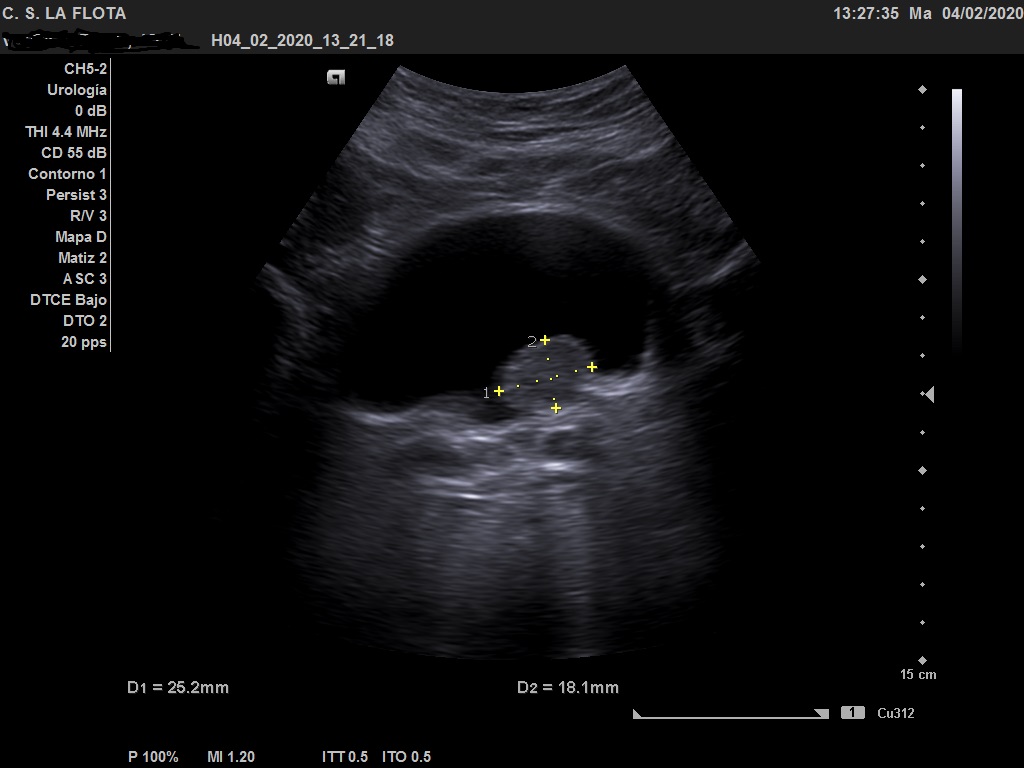

Ecografía clínica: riñones de tamaño y morfología normal, con buena diferenciación corticomedular y sin dilatacion de vias. En vejiga lesión polipoidea  de 25*18 mml.

Ante los hallazgos ecográficos se derivó al paciente a urología con copia de las imágenes. En urología solicitan cistoscopia sin precisar más pruebas de imagen.